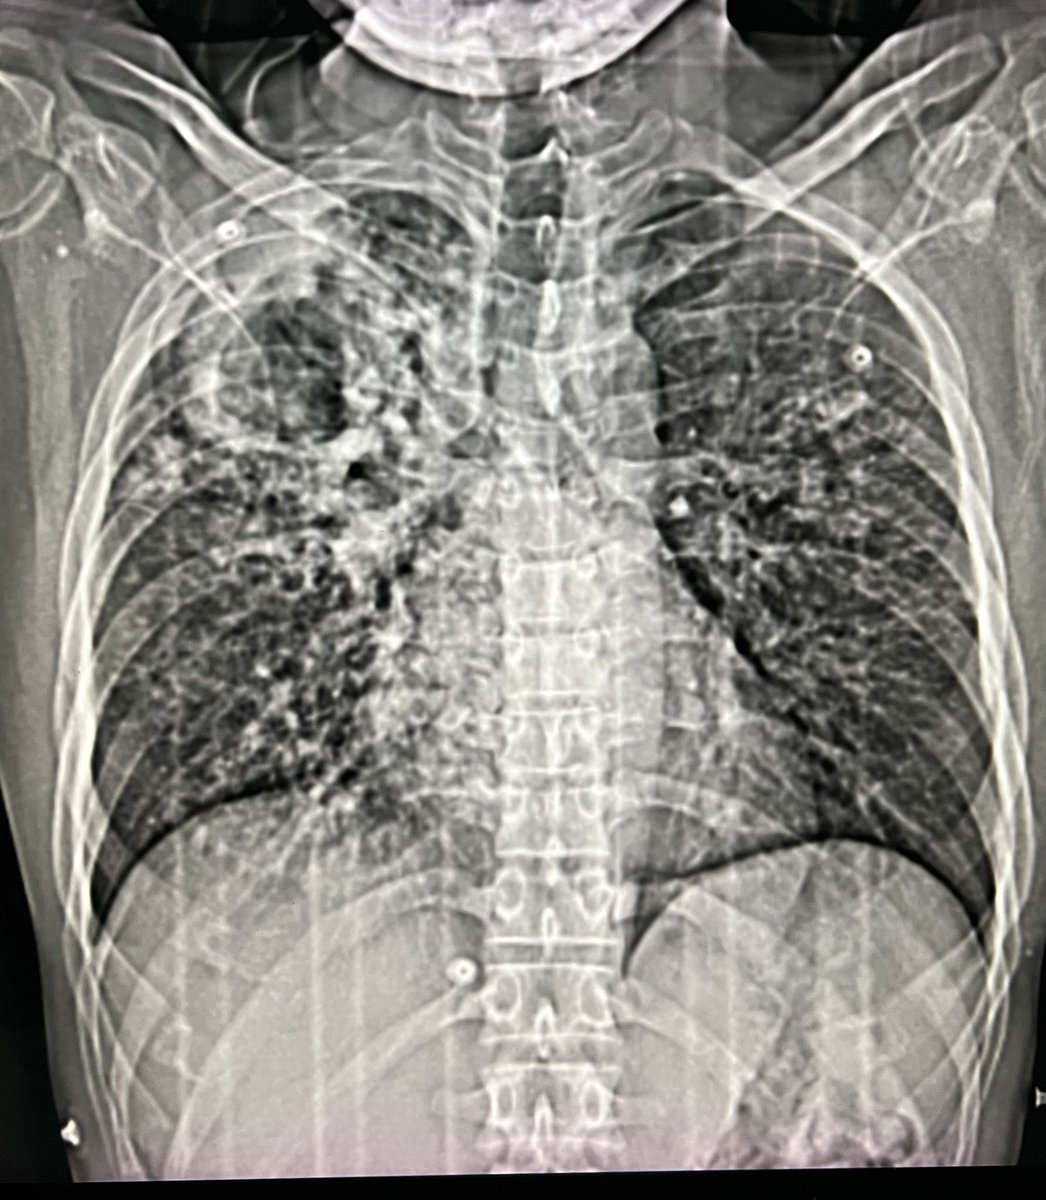

Active Pulmonary Kochs